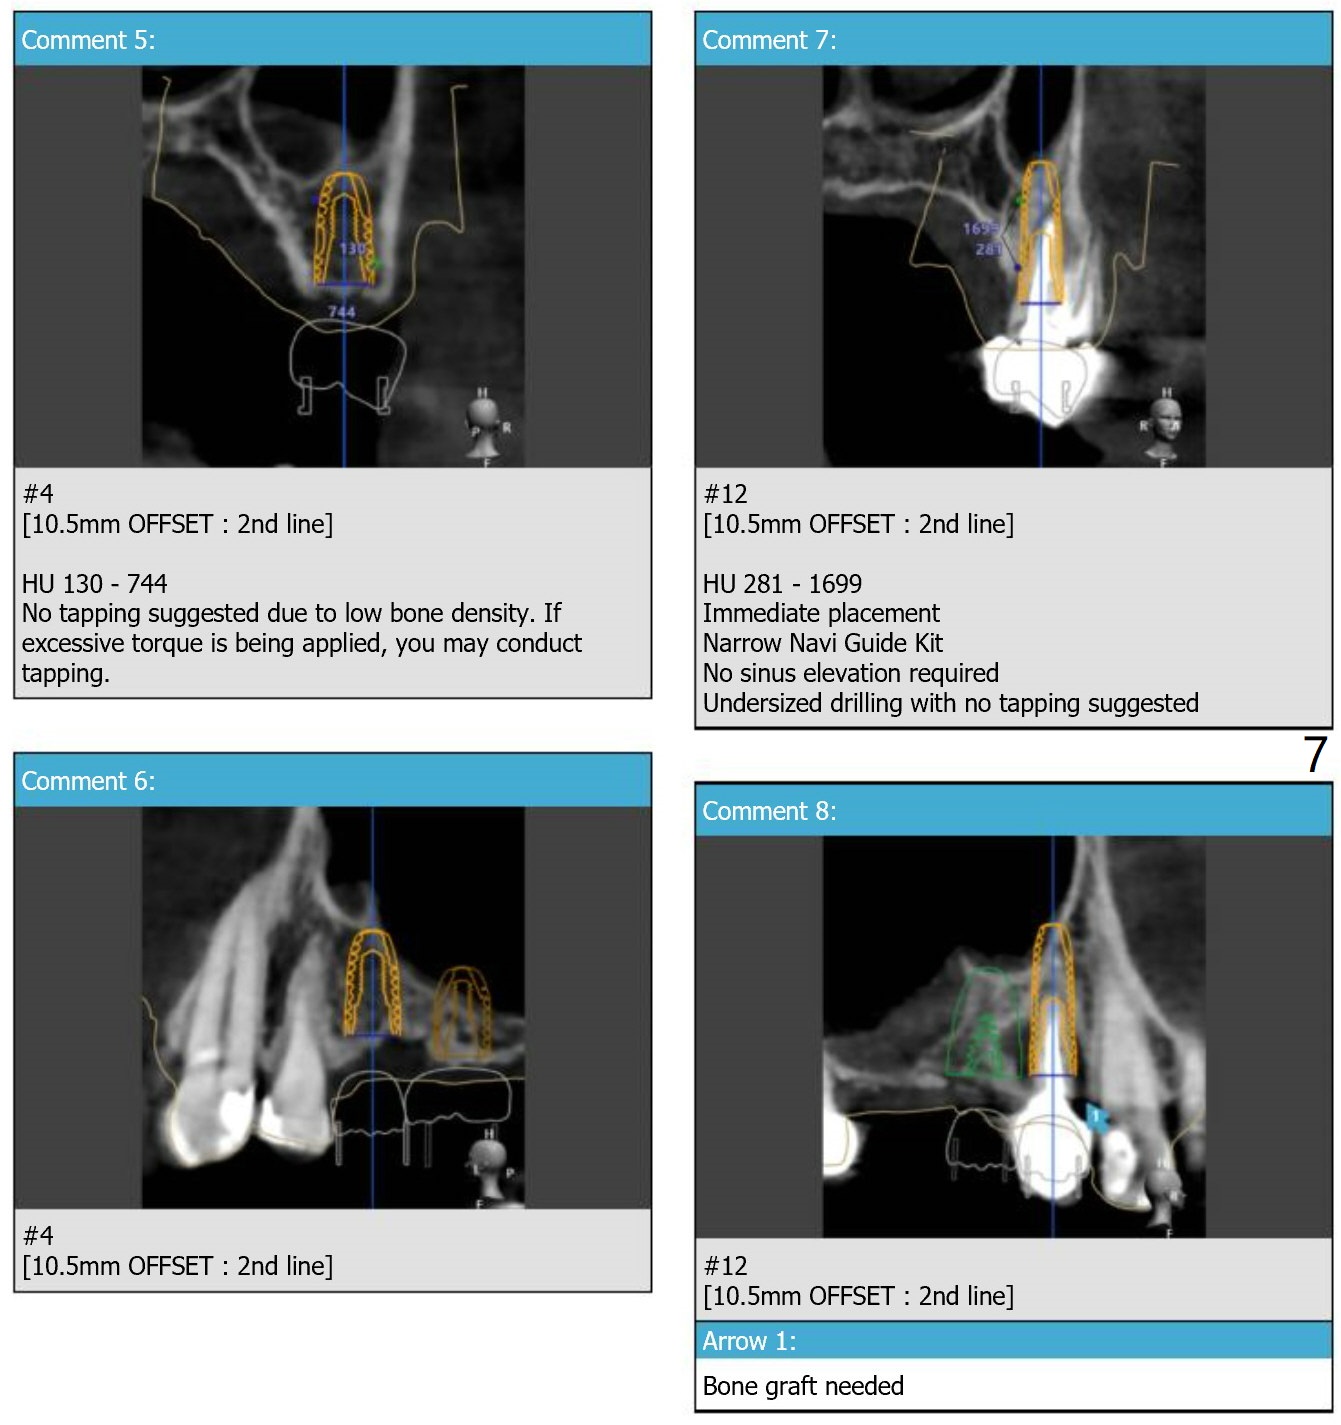

Guide for Sinus Lift

Return to Upper Arch Immediate Implant, Trajectory, No Antibiotic